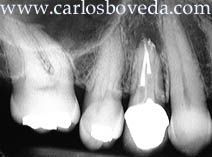

Una vista más detallada del área permite observar un ligero cambio de coloración en el cuello de la corona. Radiográficamente se nota un área radiolúcida periapical al 14. Este diente presenta una ligera sensibilidad a la percusión vertical.

Se decide proceder endodónticamente, para lo que se aísla de forma absoluta y se aborda a través de la corona. Se descubren los pernos con mucho cuidado y se vibran hasta ser extraídos. La imagen a la derecha muestra con detalle la vía de filtración de esta corona.

Se completa la remoción de irritantes presentes y la nueva preparación, y el caso se obtura con cemento sellador y gutapercha termo reblandecida. Por igual se dejan espacios para pernos en los dos conductos.

Vista radiográfica final del caso.